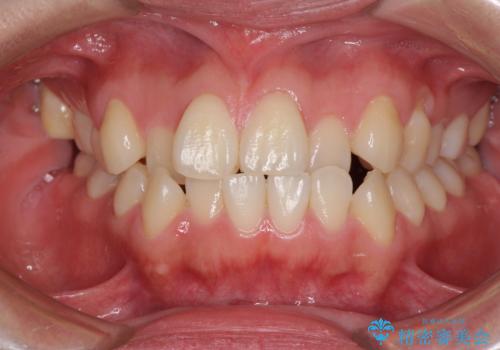

- 前歯のデコボコとクロスバイトを気にして来院された患者様です。

骨格的に下顎が前方位の受け口傾向であり、それが原因でクロスバイトとなっていました。